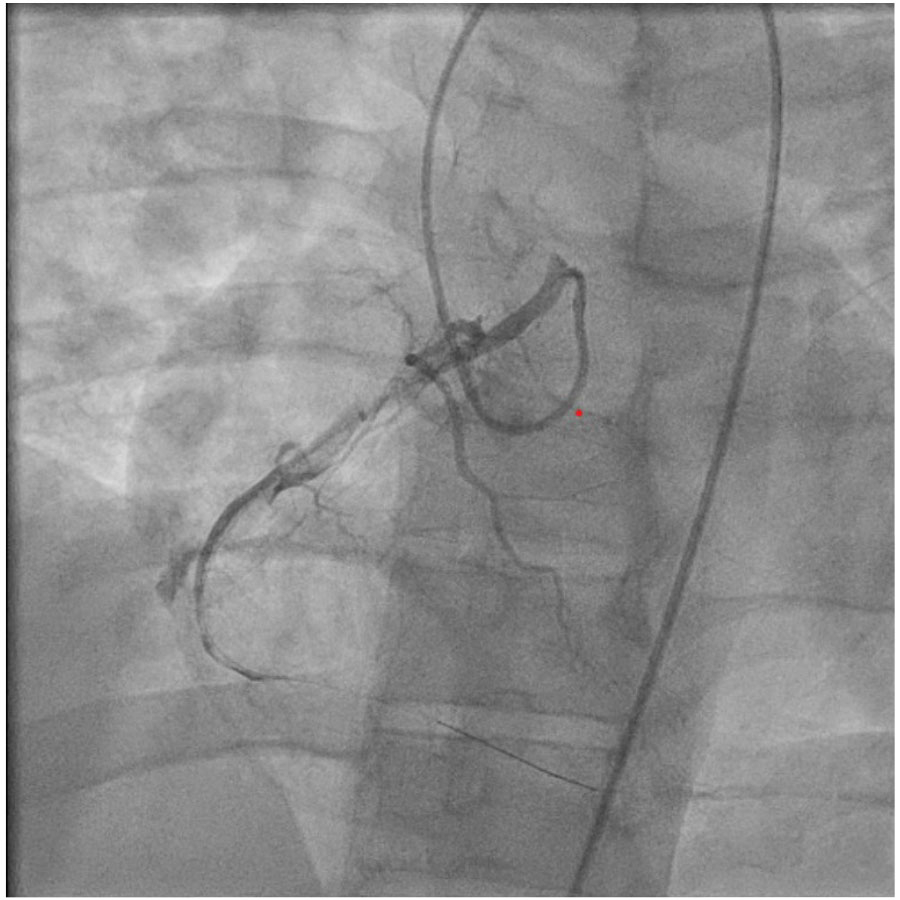

We present a 26-year-old male with dhFH due to mutations in the LDLR and APOB genes. At age 20, he presented with chest pain and was found to have an inferior myocardial infarction. His history was notable for hypercholesterolemia, managed with atorvastatin 20 mg daily, and prior tobacco use. Labs revealed an LDL-C of 214 mg/dL despite medication compliance. Left heart catheterization identified full occlusion of the right coronary artery with heavy thrombus burden and multiple aneurysms. He underwent aspiration thrombectomy and serial balloon dilations with restoration of TIMI 1 flow but persistent thrombus burden. He was discharged on therapeutic anticoagulation, ticagrelor and a week-long course of aspirin 81 mg. At follow-up, genetic counseling was pursued which revealed a dhFH genotype. Lipid-lowering treatment was intensified to a regimen of rosuvastatin 40 mg, ezetimibe 10 mg and evolocumab 140 mg SQ every 14 days, yielding a marked reduction in LDL-C to 67 mg/dL.